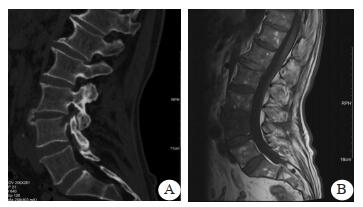

腹部CT平扫示, 十二指肠水平部增厚, 中下腹肠系膜增厚, 肠系膜静脉增粗。进一步行全腹部增强CT示, 肠系膜上动脉远端分支假性动脉瘤形成, 腹盆腔积血、积液, 肠系膜渗出。左侧髂动脉分叉处瘤样扩张。十二指肠水平部水肿增厚。双肾结石。急诊拟“肠系膜上动脉假性动脉瘤破裂出血”收住入院。入院诊断:肠系膜上动脉假性动脉瘤破裂出血、腰椎感染、心脏瓣膜置换术后、冠状动脉粥样硬化、心肌桥、高血压。

| 图 2 患者全腹部增强CT结果(示肠系膜上动脉远端分支假性动脉瘤形成, 腹盆腔积血、积液, 肠系膜渗出) |